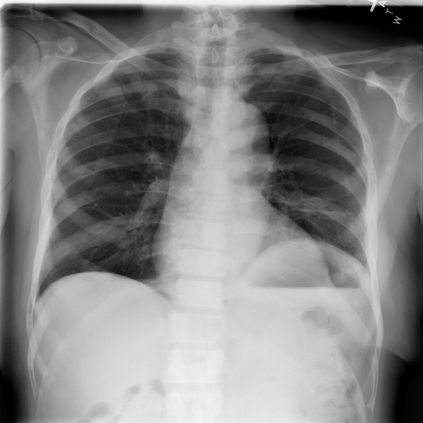

The integration of deep learning systems into healthcare has been hindered by the resource-intensive process of data annotation and the inability of these systems to generalize to different data distributions. Foundation models, which are models pre-trained on large datasets, have emerged as a solution to reduce reliance on annotated data and enhance model generalizability and robustness. DINOv2 is an open-source foundation model pre-trained with self-supervised learning on 142 million curated natural images that exhibits promising capabilities across various vision tasks. Nevertheless, a critical question remains unanswered regarding DINOv2's adaptability to radiological imaging, and whether its features are sufficiently general to benefit radiology image analysis. Therefore, this study comprehensively evaluates DINOv2 for radiology, conducting over 100 experiments across diverse modalities (X-ray, CT, and MRI). To measure the effectiveness and generalizability of DINOv2's feature representations, we analyze the model across medical image analysis tasks including disease classification and organ segmentation on both 2D and 3D images, and under different settings like kNN, few-shot learning, linear-probing, end-to-end fine-tuning, and parameter-efficient fine-tuning. Comparative analyses with established supervised, self-supervised, and weakly-supervised models reveal DINOv2's superior performance and cross-task generalizability. The findings contribute insights to potential avenues for optimizing pre-training strategies for medical imaging and enhancing the broader understanding of DINOv2's role in bridging the gap between natural and radiological image analysis. Our code is available at https://github.com/MohammedSB/DINOv2ForRadiology